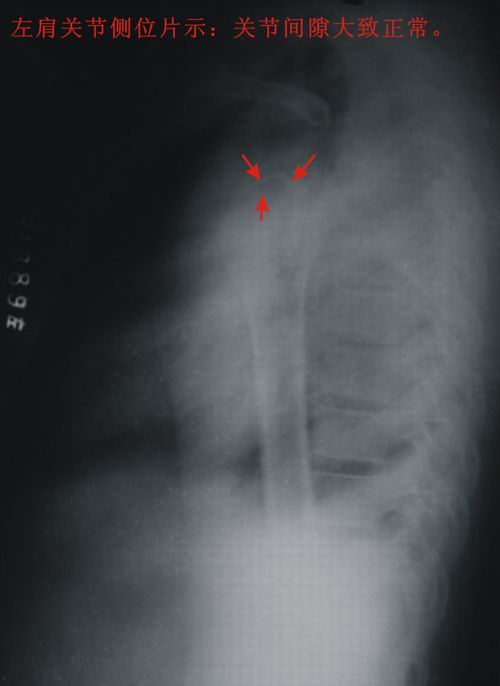

患者,男,13岁。自诉两月前双肩关节时有弹响,有时左、右肩关节轮换隐痛。但双上肢能抬举、左右旋转、屈伸自如。pe:双肩及双上肢皮肤无红、肿。触诊:双肩关节区域有抖动,似触心脏的搏动感,但抖动、搏动感能自控。双肩区域皮肤无发热。听诊:用耳贴近患者双肩区能听到弹响声。x线胸部后前位示:双肩关节间隙增宽,考虑双肩关节半脱位。双肩关节正侧位片示:双肩关节无明显脱位征象。双肩关节区域透视示:双肩关节解剖位时,双肩关节间隙增宽(与胸部后前位的双肩关节间隙相等),也能见双肱骨头在双肩关节腔内上、下移动约1cm左、右。但患者能自控(双肱骨头在双肩关节腔内不上、下移动)。请战友们详见患者相片、胸部后前位片、双肩关节正侧位片。我第一次碰到这样的病例(是否是神经性关节病“夏科氏关节”?),经验不足,希望能帮助诊断。亦请分析病因、病理机制,是什么原造成的?最好能提供治疗方法,谢谢!

双侧肩关节解剖位时,双肩关节间隙增宽,但肱骨头及周边骨质 关节腔均未见异常。与骨科专家会诊结果,目前只能诊断:肩关节松弛症!

双肩关节间隙增宽,但肱骨头及周边骨质 关节腔均未见异常。